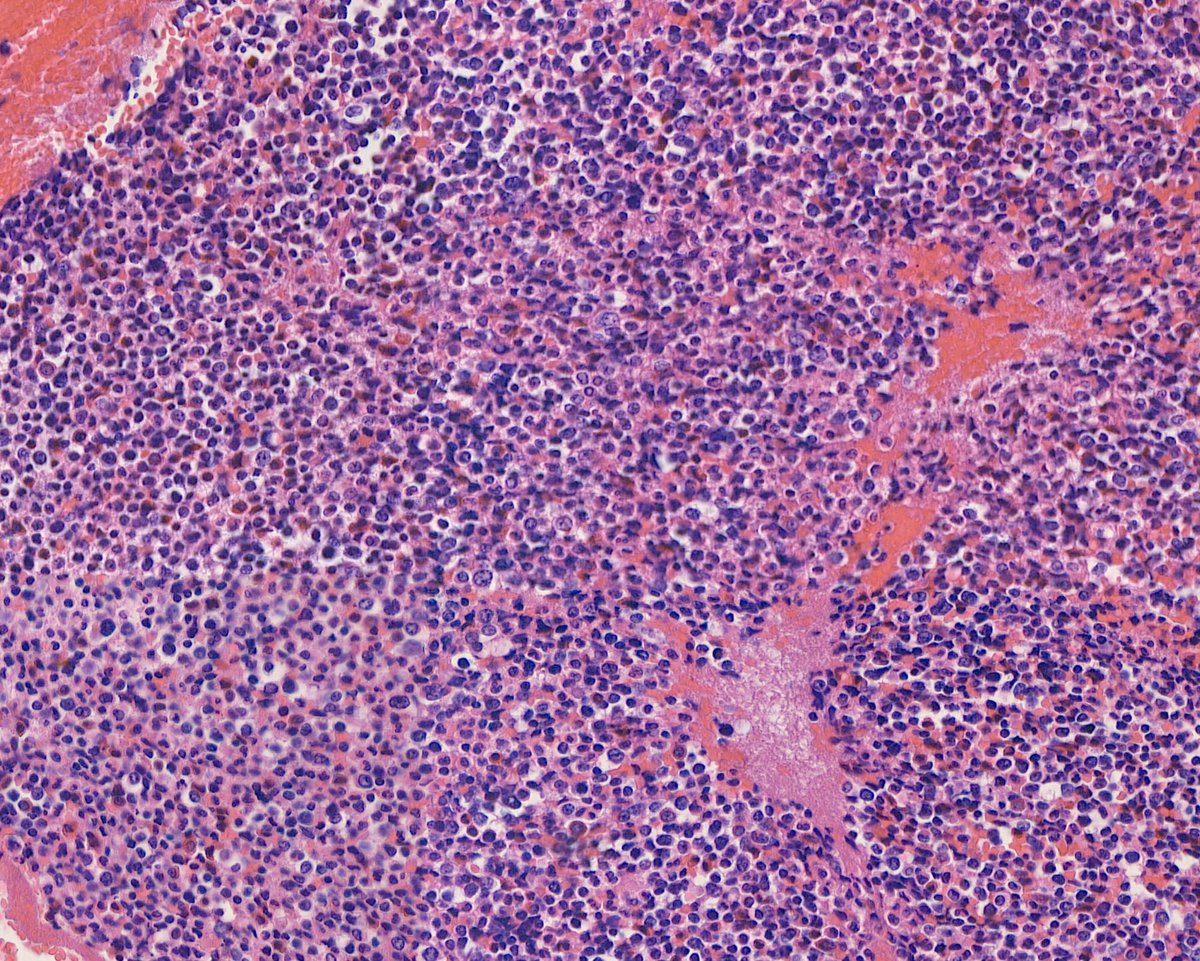

Enhorabuena a Elena María García Pastor, residente del Hospital Universitario Virgen de la Victoria (Málaga), por ser la autora de nuestro #CasoDelMes de OCTUBRE 2025. https://t.co/Kp4XYkBXcj